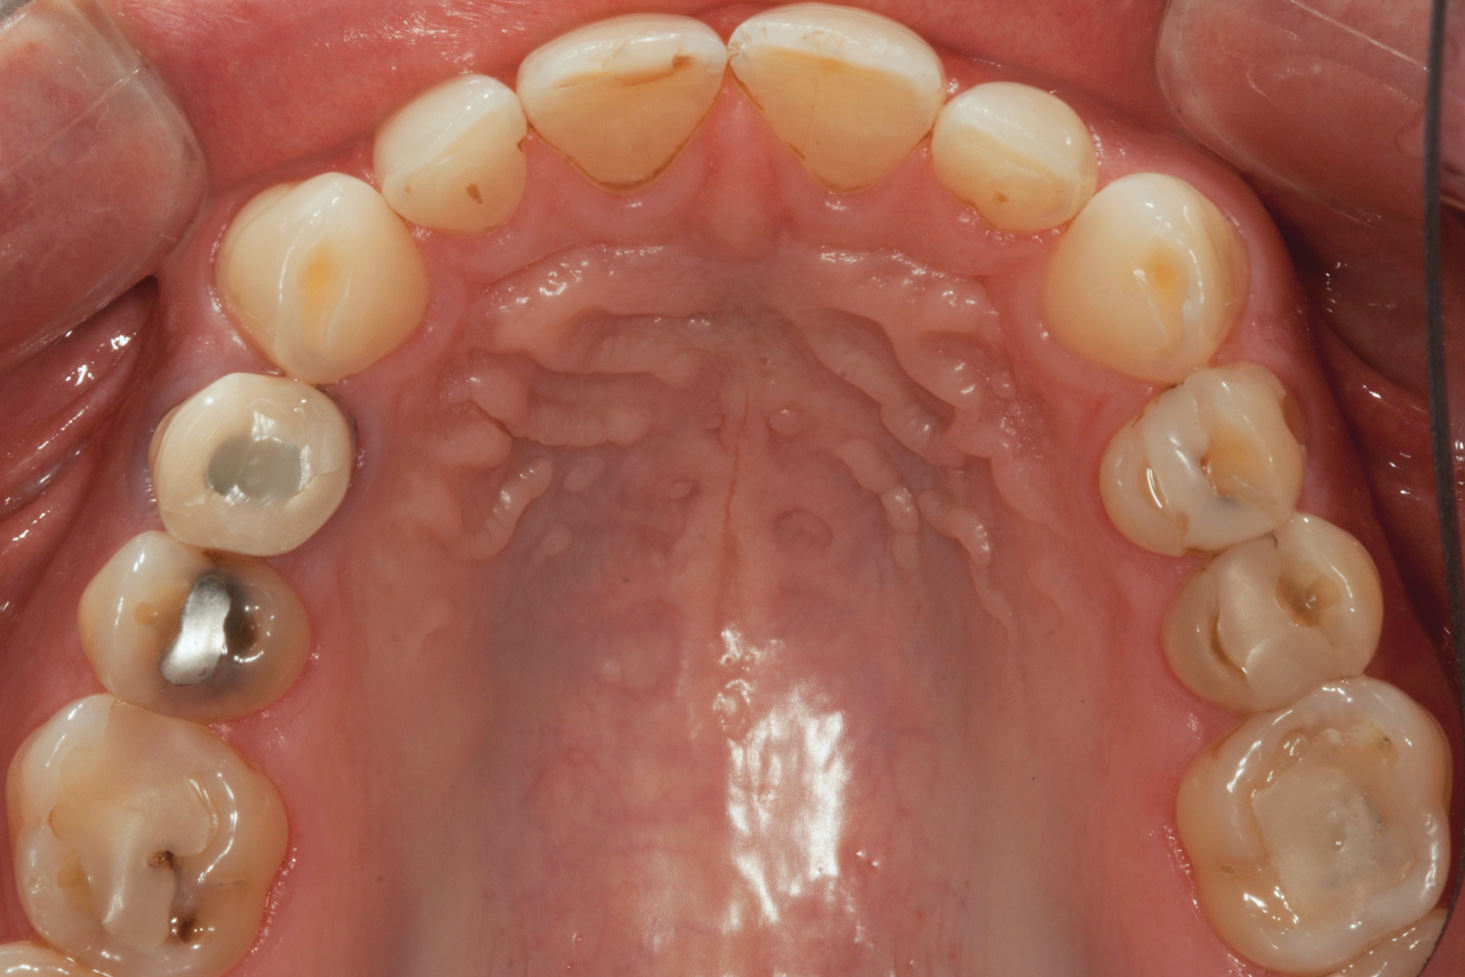

(4.) Preoperative occlusal view of upper arch.

Figure 4

A comprehensive examination was carried out, and preoperative photographs were taken (Figure 1 through Figure 4). The patient presented with fair oral hygiene and slight, generalized tissue inflammation. Caries and defective restorations were detected on teeth Nos. 4, 5, 13, and 14. The crown on tooth No. 12 was showing signs of leakage, and although the endodontic access cavity had been temporarily restored with composite, this endodontic re-treatment was acceptable and the tooth was otherwise symptom-free. Erosion was present on most of the posterior teeth and the cuspids, and abrasion was noted on teeth Nos. 4, 5, 10, 11, 20, 21, 22, 28, and 29. An examination of the patient's muscles, joints, and bite revealed no joint sounds, a normal range of motion, and negative joint load and immobilization tests.

The dentofacial examination revealed a low smile line with no incisor display when the lips were in repose. The anterior teeth were chipped and worn, and their overall color was darkened. The buccal corridors were deficient, and the failing crown on tooth No. 12 was visible in a full smile.